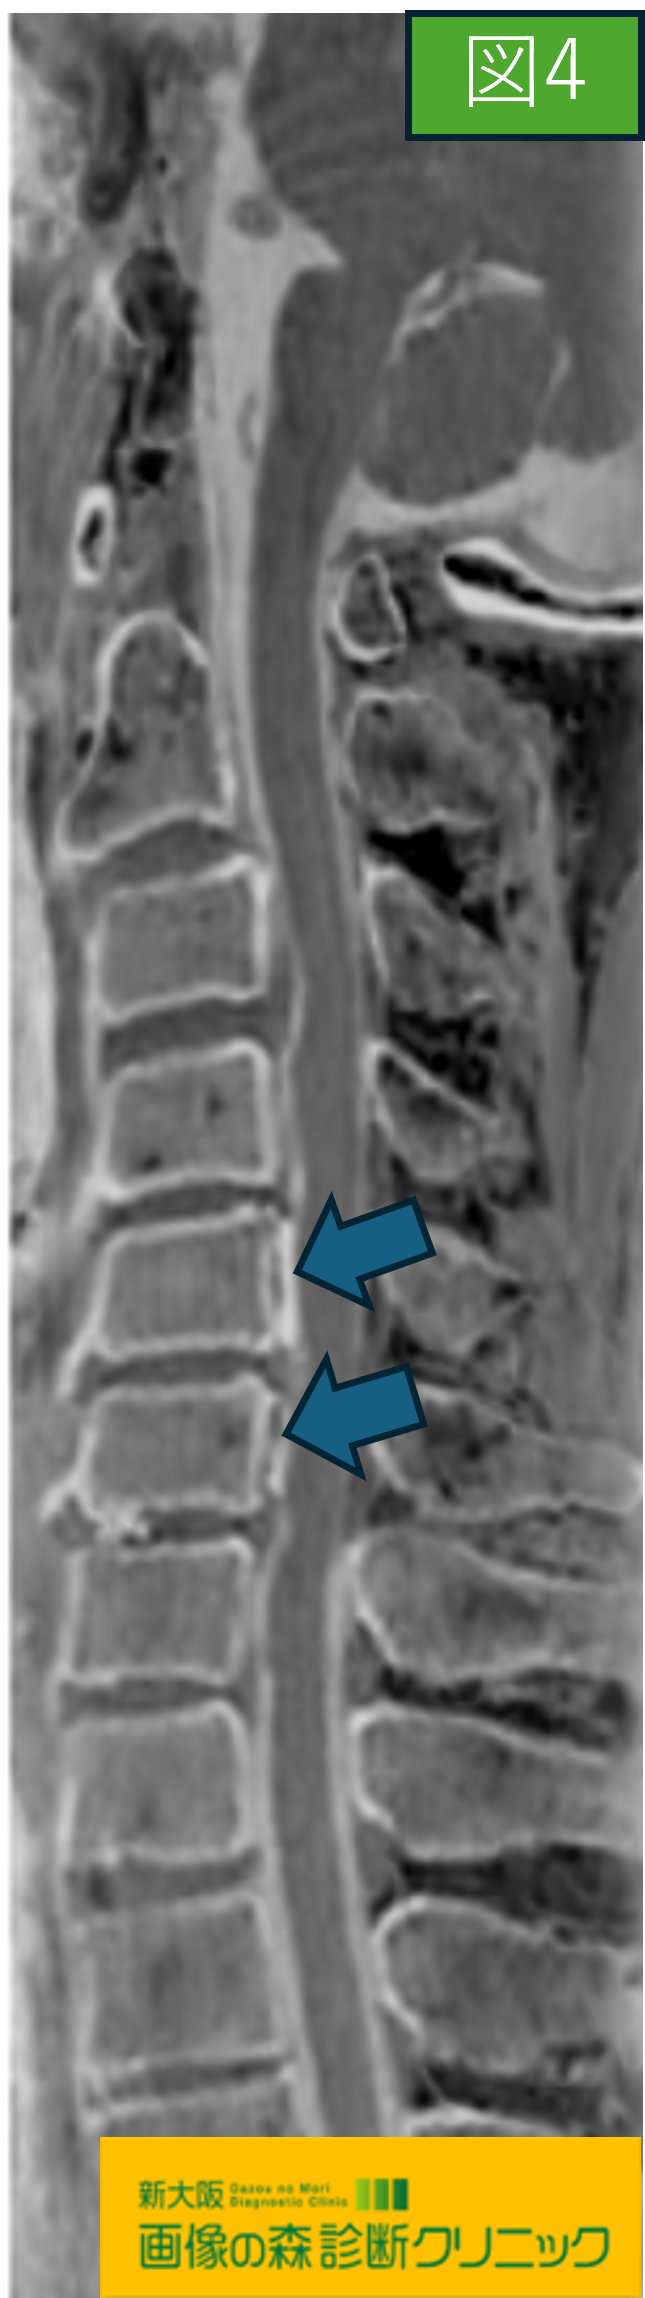

図3・図4では頚椎MRI画像で、どちらも

後縦靭帯骨化症(OPLL)の症例です。

図4の画像はBone Imageと言ったMRIの撮像方法の一種で

図1の様なCTに似た画像の描出が可能です。

被ばくの心配がなくCTと同様な画像が得られるため、

腰椎の分離症などでも撮像することが多くあります。